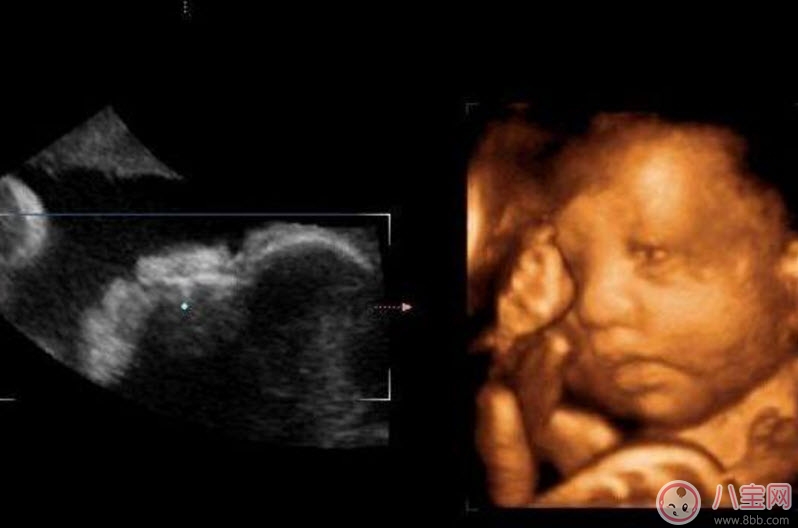

二維超聲可以理解為我們通常說的B超,顯示的是斷面圖像。何為斷面圖像?就是把西瓜切開,你在屏幕上只能看到西瓜的切面(斷面),但經(jīng)驗(yàn)豐富的你,可以只看這個(gè)切面(斷面)就知道這是一個(gè)西瓜。

三維、四維超聲就是把很多個(gè)二維斷面圖像通過計(jì)算機(jī)重建成一個(gè)立體的圖像。相當(dāng)于把切成很多片的西瓜,重新堆疊成一個(gè)完整的西瓜,這個(gè)堆疊過程由計(jì)算機(jī)完成。三維、四維的區(qū)別在于,三維是照片,四維是影片,四維就是會(huì)動(dòng)的三維照片(實(shí)時(shí)三維)。